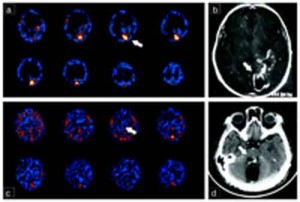

L’analisi genetica di un paziente turco il cui cervello manca delle caratteristiche circonvoluzioni cerebrali del cervello umano ha permesso di rivelare che la deformità era causata dalla delezione di due singole “lettere” in un gene, quello per la laminina gamma 3 (LAMC3), una mancanza riscontrata anche in due altri pazienti con un’anomalia analoga.